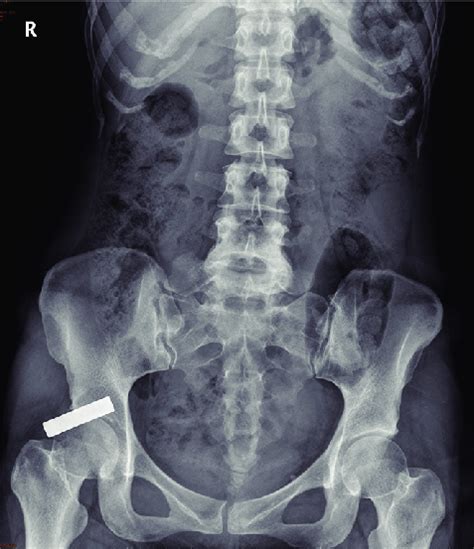

Gas in your digestive system is part of the normal process of digestion. Infectious disease 34 years experience. Web sometimes it indicates a disorder such as: Unremarkable in medical terms means normal. What does liver, spleen, pancreas, and adrenals are unremarkable. If the visualized bowel gas in your. Web download scientific diagram | the supine abdominal radiograph showed unremarkable bowel gas pattern in the abdomen. Getting rid of excess gas, either. Web a nonspecific bowel gas pattern may be caused by factors, such as: Web if the visualized bowel gas in your imaging study was unremarkable, that means it didn't look like it was indicating.

If the visualized bowel gas in your. Web see the page on normal bowel gas pattern. Web sometimes it indicates a disorder such as: Everyone passes gas several times daily. Web a nonspecific bowel gas pattern may be caused by factors, such as: Web in the colon, bacteria act on these foods, which causes the gas. Web see answer (1) best answer. Web download scientific diagram | the supine abdominal radiograph showed unremarkable bowel gas pattern in the abdomen. Web the axr demonstrates extensive linear gas shadowing with characteristic extension to the peripheries of the liver. Web 1 doctor answer • 1 doctor weighed in. Web normal bowel gas pattern is important to identify in order to diagnose and locate radiologically abnormal bowel gas.